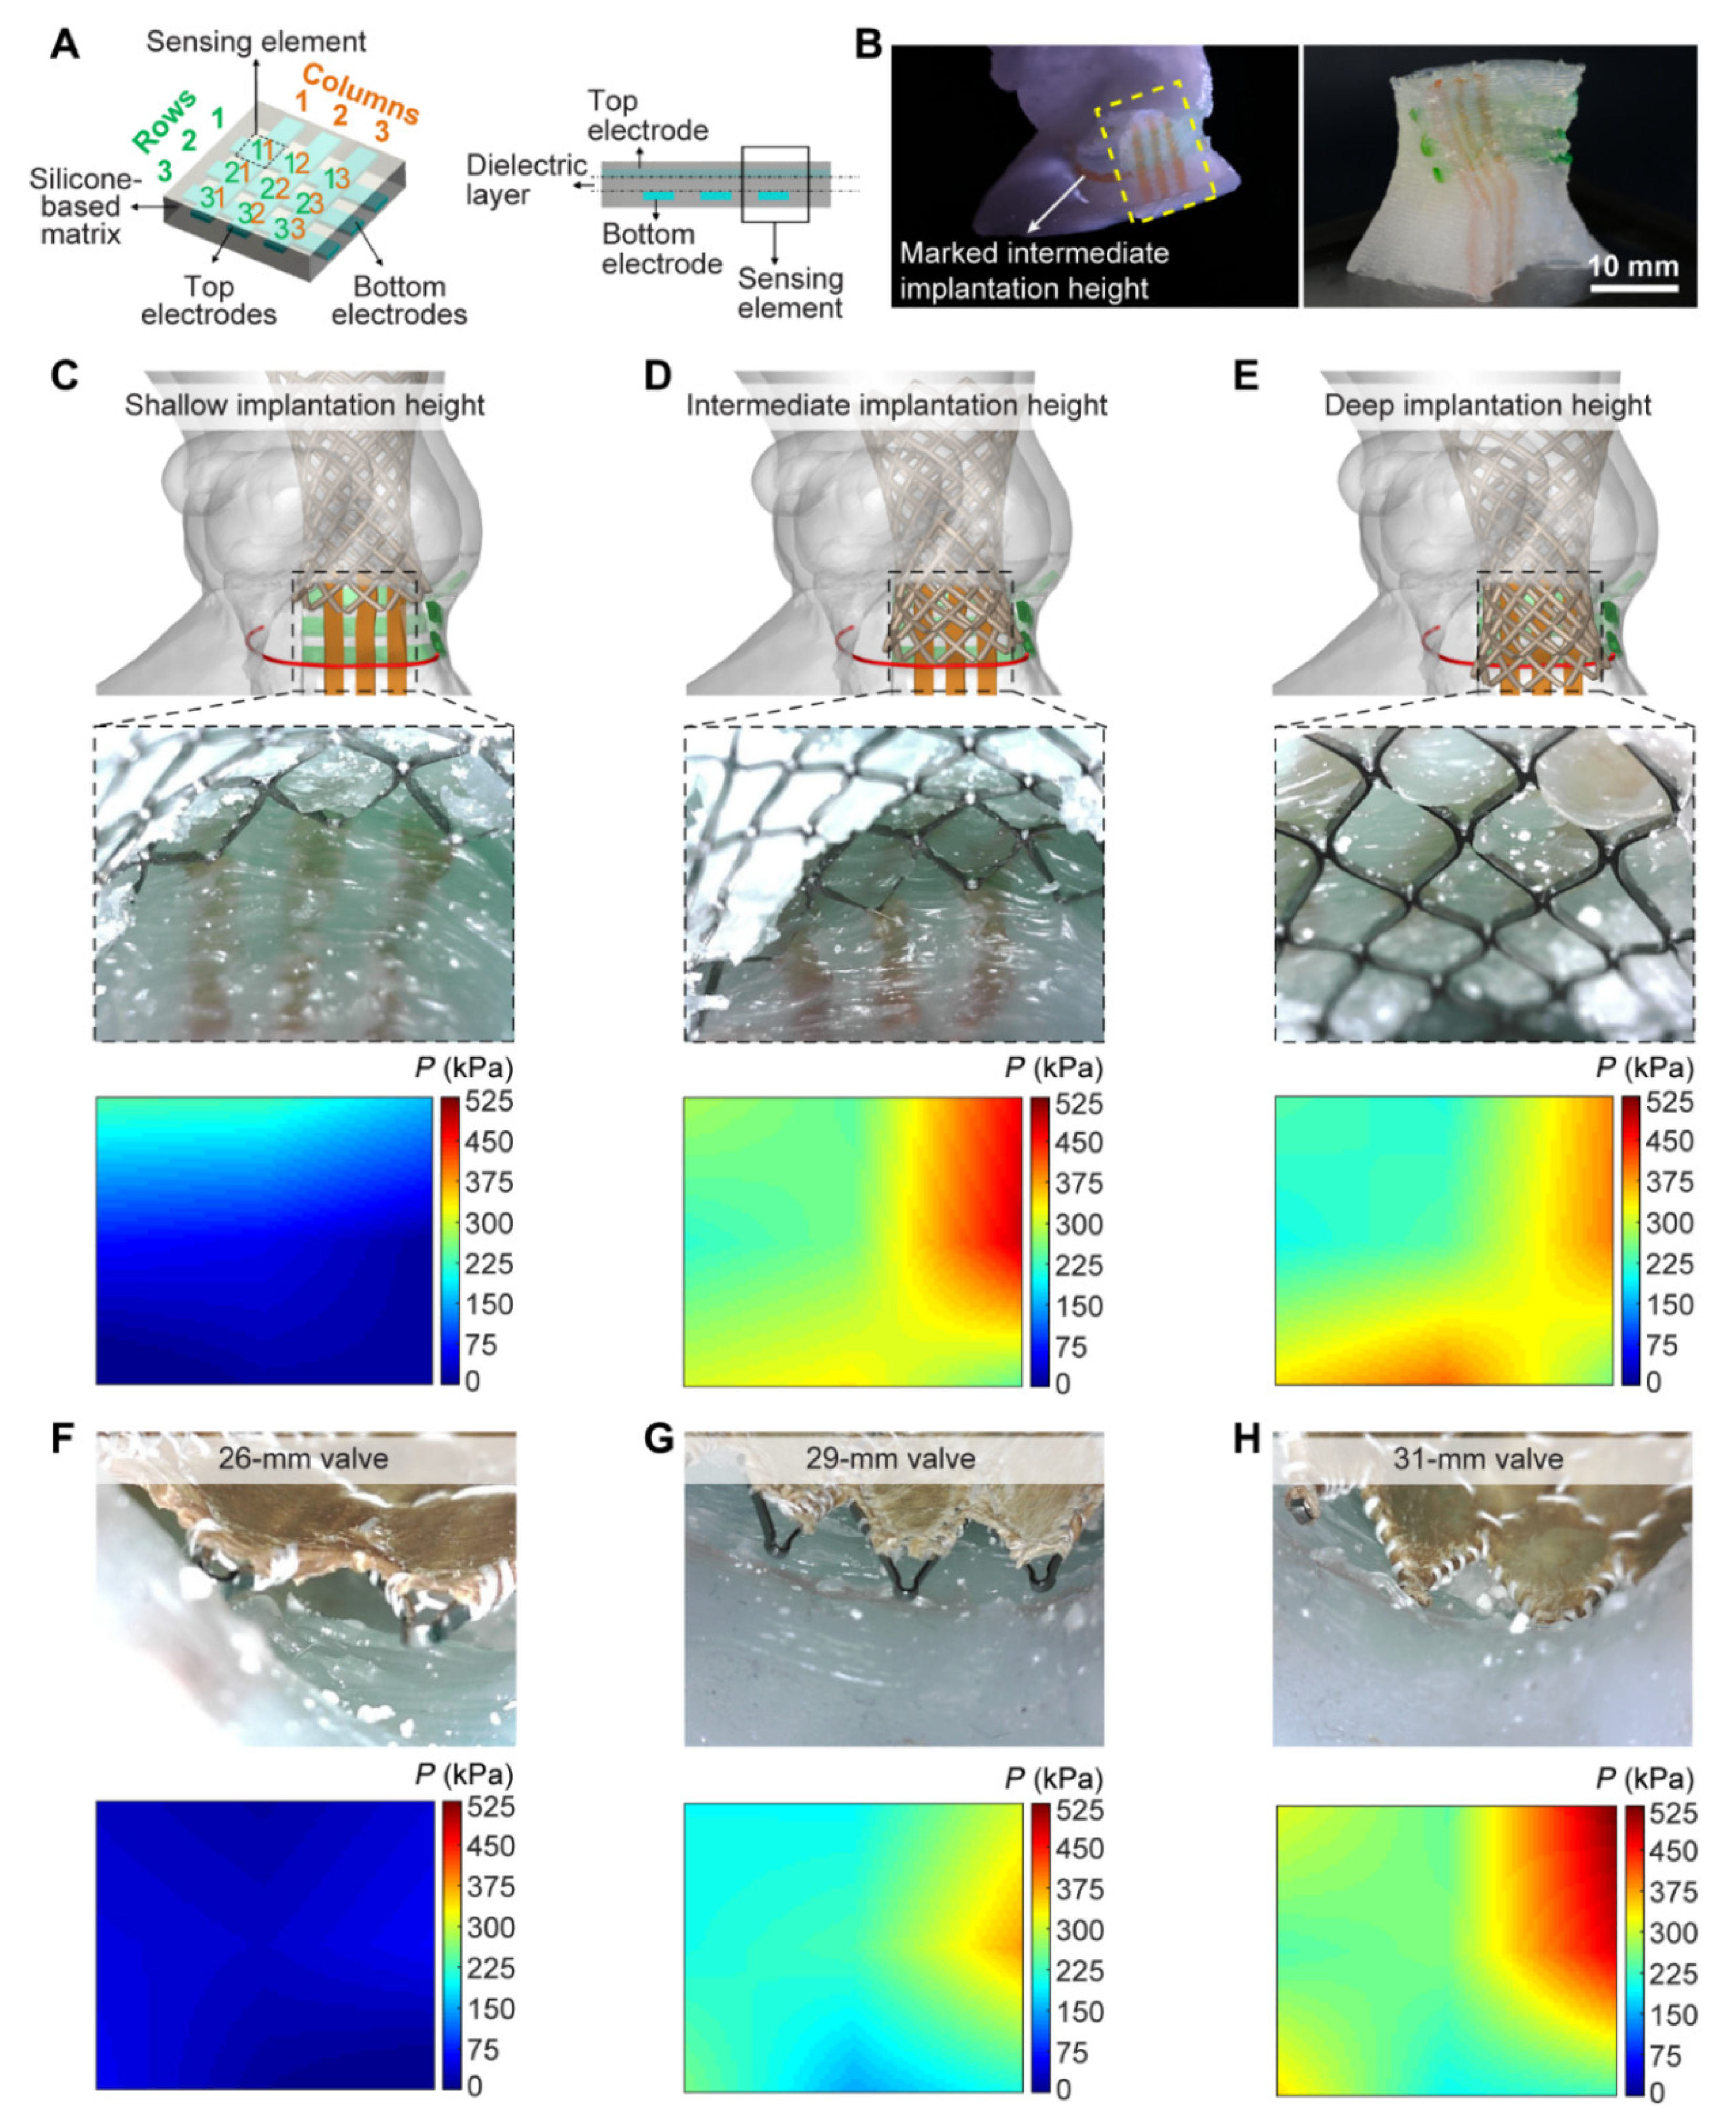

- Haghiashtiani, G.; Qiu, K.; Zhingre Sanchez, J.D.; Fuenning, Z.J.; Nair, P.; Ahlbeeg, S.E.; Iaizzo, P.A.; McAlpine, M.C. 3D printed patient-specific aortic root models with internal sensors for minimally invasive applications. Sci. Adv. 2020, 6, eabb4641. [Google Scholar] [CrossRef] [PubMed]

- Sun, Z.; Ng, C.K.; Squelch, A. Synchrotron radiation computed tomography assessment of calcified plaques and coronary stenosis with different slice thicknesses and beam energies on 3D printed coronary models. Quant. Imaging Med. Surg. 2019, 9, 6–22. [Google Scholar] [CrossRef] [PubMed]

- Sun, Z. 3D printed coronary models offer new opportunities for developing optimal coronary CT angiography protocols in imaging coronary stents. Quant. Imaging Med. Surg. 2019, 9, 1350–1355. [Google Scholar] [CrossRef] [PubMed]

- Sun, Z.; Jansen, S. Personalized 3D printed coronary models in coronary stenting. Quant. Imaging Med. Surg. 2019, 9, 1356–1367. [Google Scholar] [CrossRef] [PubMed]